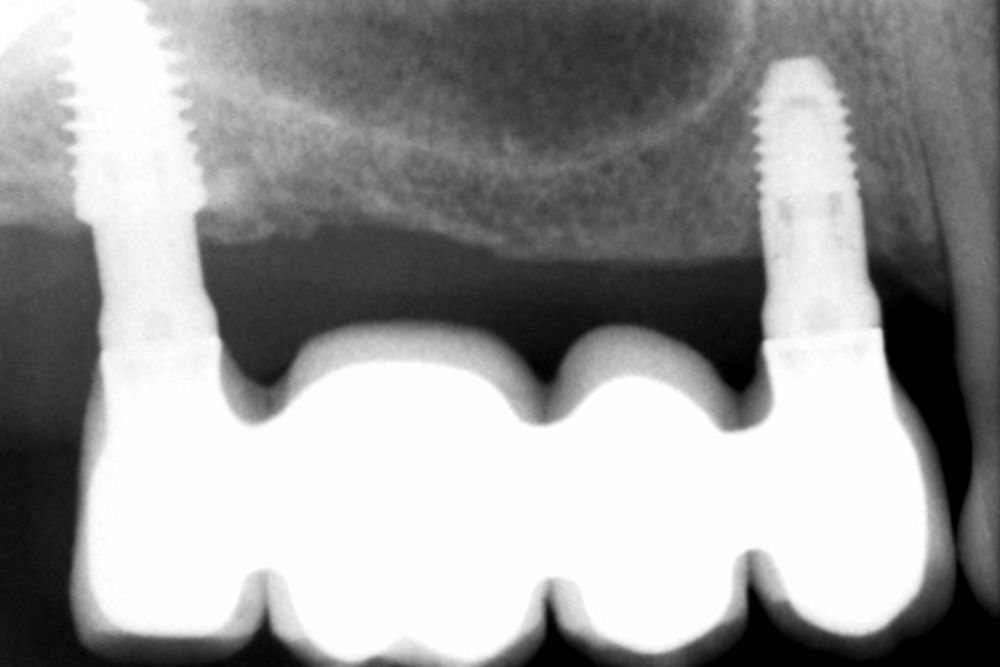

Una vez colocados los implantes, podemos realizar incluso carga inmediata, ya que, aun en condiciones de baja densidad y escasa altura ósea residual, con el protocolo anteriormente descrito se logra la estabilidad primaria suficiente (Figuras 25 y 26). Elaboramos una prótesis de carga inmediata atornillada sobre transepitelial (colocados en el momento de la cirugía y mantenidos posteriormente para no romper el hermetismo), confeccionada en resina con una estructura de barras articuladas. Esta prótesis nos proporciona carga progresiva mientras se produce la integración de los implantes, lo que favorece este proceso y permite reconstruir el patrón oclusal perdido, dado que presenta múltiples ausencias dentales del sector posterior maxilar. La carga progresiva en los implantes dentales es una técnica que permite una transición gradual de fuerzas sobre el implante, favoreciendo la adaptación biológica y la estabilidad ósea a lo largo del tiempo. En lugar de aplicar una carga inmediata completa, se introduce una presión controlada y creciente durante el periodo de cicatrización, lo que facilita una mejor osteointegración y reduce el riesgo de sobrecarga temprana. Este enfoque es especialmente útil en casos donde la calidad ósea es comprometida o cuando se busca una mayor predictibilidad en el tratamiento12.

Transcurridos 6 meses desde la carga inicial progresiva, se puede elaborar la prótesis definitiva, trasladando los parámetros de la prótesis provisional (Figura 27). La paciente continúa en seguimiento durante un año, realizándose radiografías de control para el monitoreo del hueso crestal, sin encontrarse pérdida ósea asociada en ninguno de los implantes (Figuras 28-29).